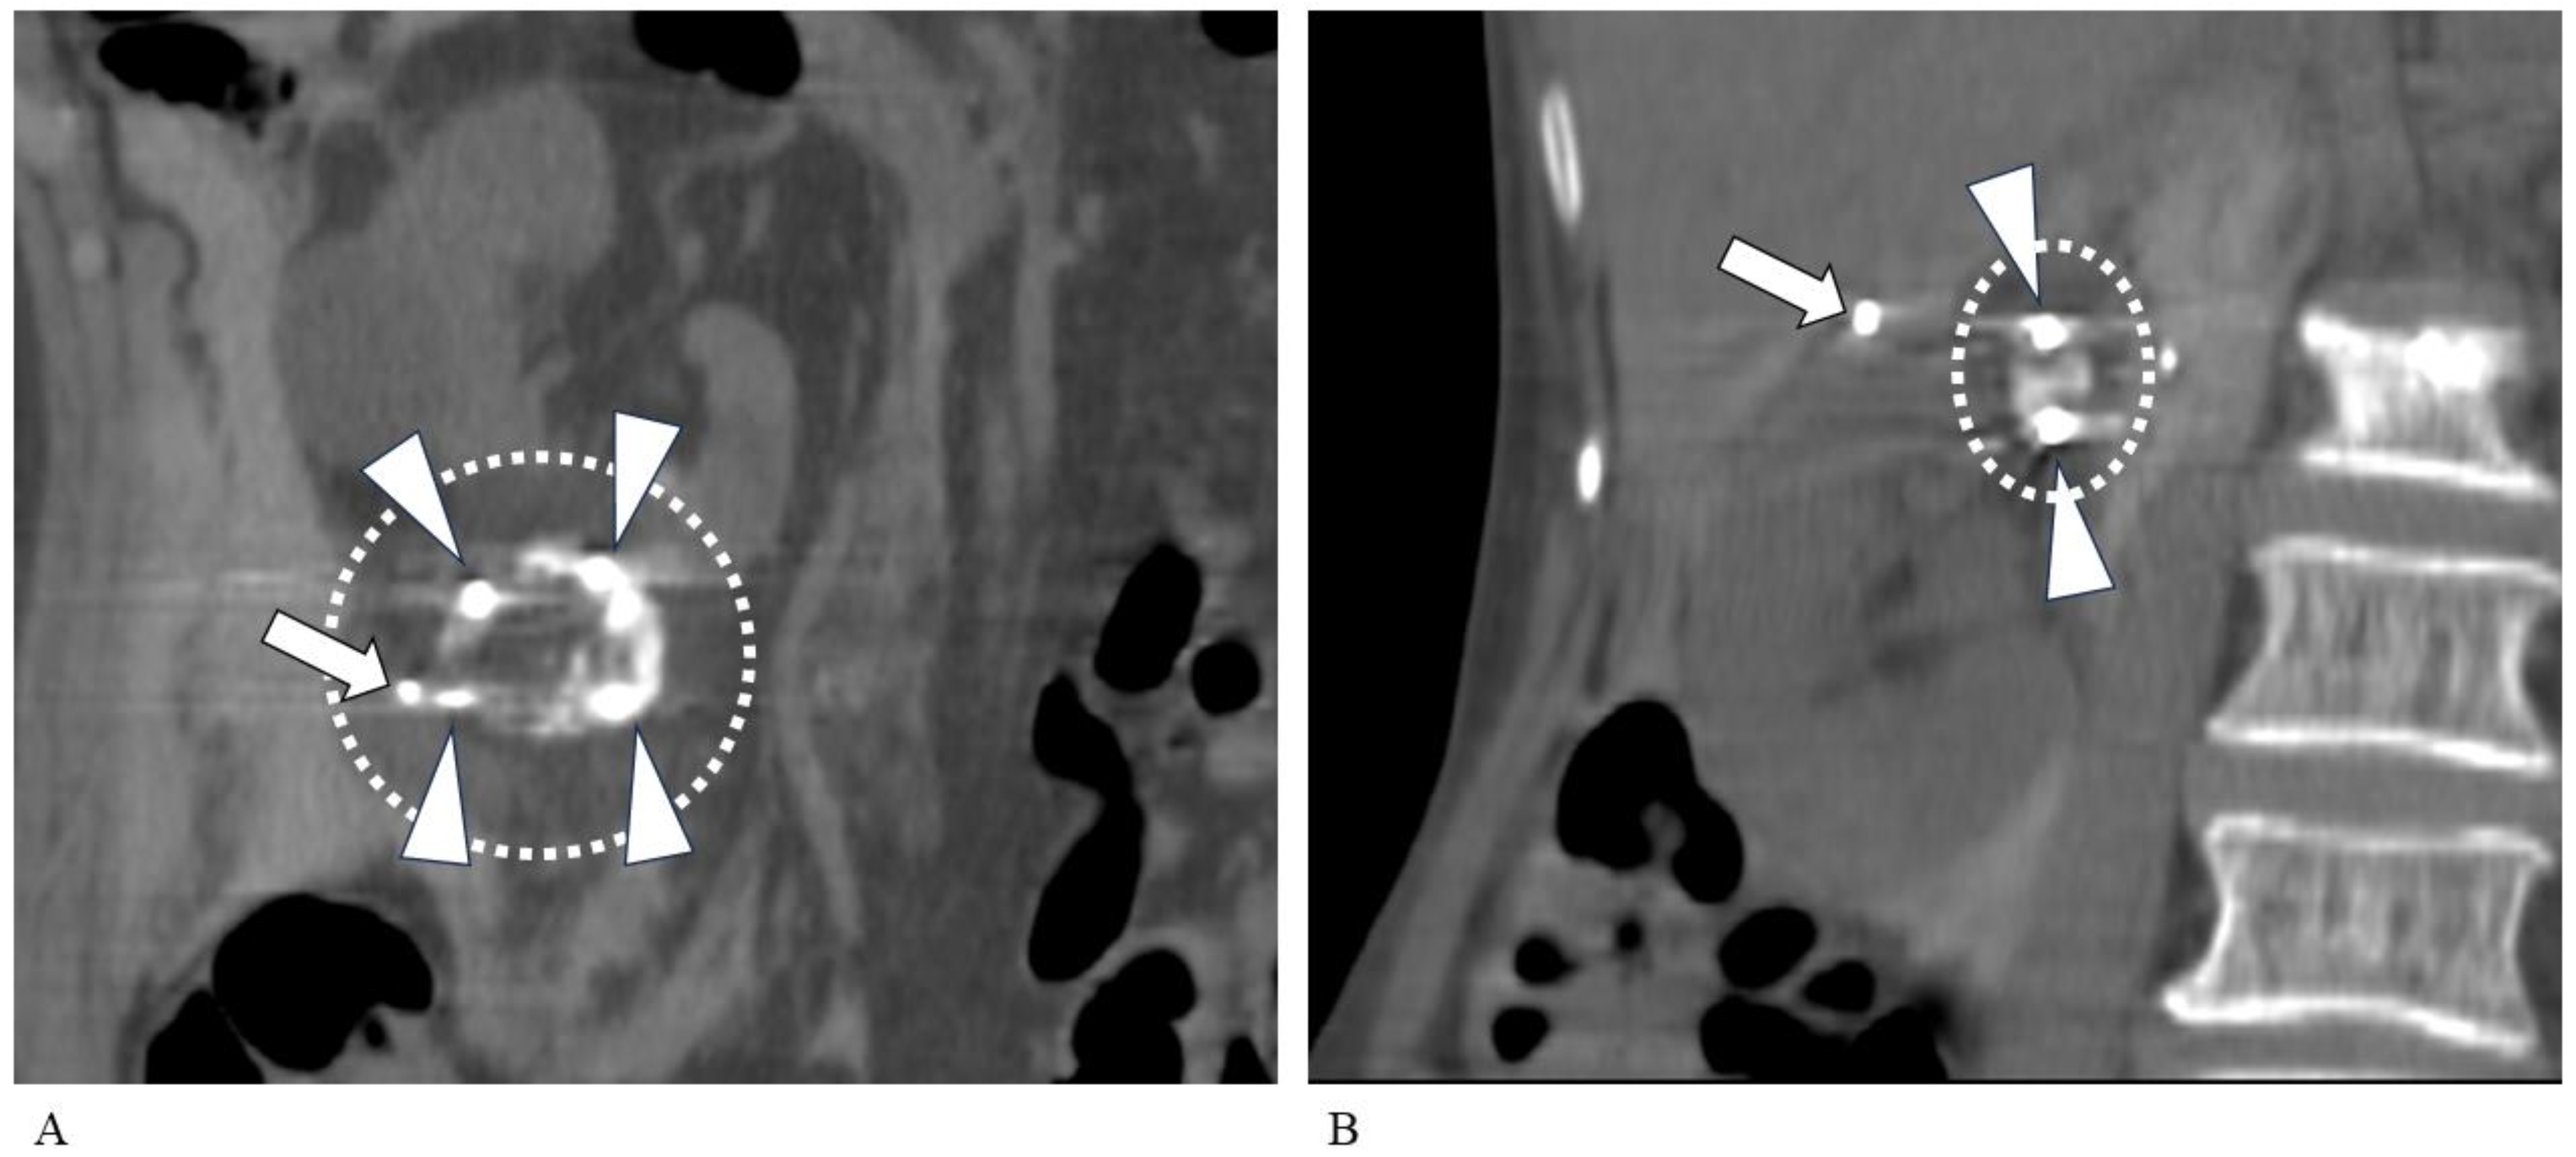

2.2. TAE Technique

2.3. PCA Technique